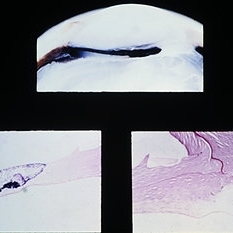

Hyaloid artery extending into the vitreous cavity from the optic nerve head. (E.P. No. 16127)

Condition/keywords: hyaloid artery, optic nerve head, vitreous cavity

Examples of Bergmeister's papilla. Note the strands of vitreous, composed of glial cells, attached to the papilla. The presence of a small vessel within the Bergmeister's papilla (lower right) suggests that its origin is related to the hyaloid artery. (E. P. Nos. 31888,38589, 29360, and 32239)

Condition/keywords: Bergmeister's Papillae, glial cells, vitreous